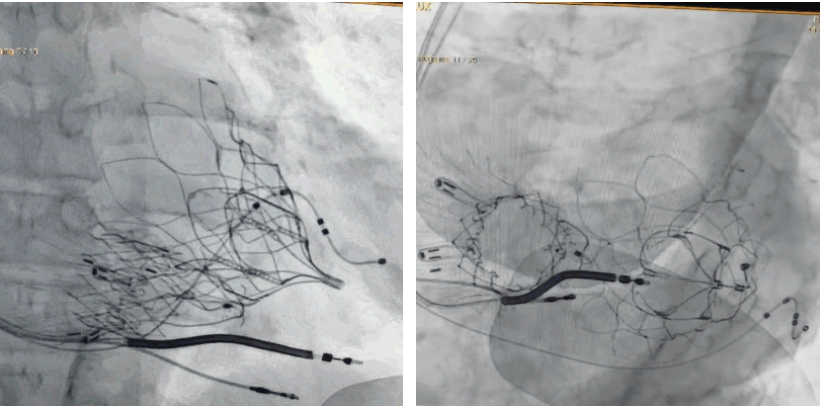

術(shù)后DSA顯示Lux-Valve Plus與Tendyne和ICD無(wú)相互影響

手術(shù)在全麻狀態(tài)下進(jìn)行。術(shù)者采用經(jīng)右側(cè)頸靜脈入路的方式將輸送器送入患者心臟內(nèi),在TEE及DSA引導(dǎo)下調(diào)整輸送器頭端角度,使得輸送器與三尖瓣瓣環(huán)平面垂直。在輸送器進(jìn)入右心室后釋放室間隔錨定裝置,而后釋放瓣葉夾持件(2個(gè)耳片結(jié)構(gòu))成垂直狀態(tài)。在TEE及DSA確定夾持件固定至三尖瓣葉根部且位于右室側(cè)后釋放人工瓣心房側(cè)盤片。隨后調(diào)整瓣膜同軸性以及室間隔錨定件位置(貼合室間隔),前推藏針管并固定,進(jìn)而釋放室間隔錨定裝置,并再次確認(rèn)瓣膜位置、穩(wěn)定性及同軸性,合攏輸送鞘后撤出輸送器,完成LuX-Valve Plus人工三尖瓣瓣膜的植入,僅殘余微量瓣周漏。且經(jīng)手術(shù)中心電生理團(tuán)隊(duì)評(píng)估,病人的起搏器和ICD功能沒(méi)有受到影響。

LuX-Valve Plus經(jīng)血管三尖瓣置換系統(tǒng)此次“出海”圓滿完成,術(shù)后Rodrigo Estévez-Loureiro教授對(duì)LuX-Valve Plus經(jīng)血管三尖瓣置換系統(tǒng)的器械性能和治療效果大為稱贊,認(rèn)為L(zhǎng)uX-Valve Plus的手術(shù)體驗(yàn)非常好。術(shù)后即刻超聲顯示三尖瓣反流幾乎完全消失,血流動(dòng)力學(xué)改善顯著,患者恢復(fù)快。在面對(duì)復(fù)雜解剖結(jié)構(gòu)、超聲影像質(zhì)量不佳、有起搏導(dǎo)線干擾時(shí),Lux-Valve Plus也體現(xiàn)了極強(qiáng)的適應(yīng)性。Thomas Modine教授和Anson Cheung教授也肯定了LuX-Valve Plus術(shù)中操作的便捷性,認(rèn)為L(zhǎng)uX-Valve Plus容錯(cuò)率高,對(duì)術(shù)中影像的依賴較小,后期希望可以更多的應(yīng)用LuX-Valve Plus三尖瓣置換系統(tǒng)于臨床實(shí)踐,讓更多的三尖瓣重度反流患者盡早獲益,改善預(yù)后。